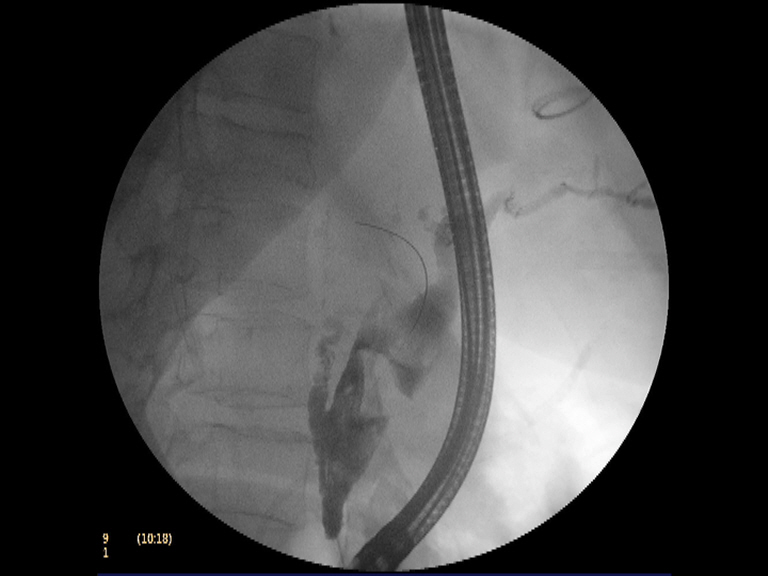

Paciente mujer de 82 años de edad con antecedentes de DM tipo II en tratamiento con insulina y síndrome de bradi-taquiarrtimia (portadora de marcapasos). Ingresa en el hospital por una fractura de cadera que se interviene quirurgicamente. Tras la intervención se practica un control analítico donde se aprecia una elevación de la GGT (519 UI/l) asintomática. La ecografía subsiguiente refleja una importante dilatación de la vía biliar (intra y extrahepática), con un colédoco de 22 mm, en cuyo interior se observa una coledocolitiasis de gran tamaño (22 mm), así como una colelitiasis en el contexto de una vesícula escleroatrófica. Se decide realizar CPRE para extracción de la coledocolitiasis. la canulación es sencilla, observando en la colangiografía una marcada dilatación de la vía biliar extrahepática (> 20 mm) con varias coledocolitiasis, dos de ellas de gran tamaño (unos 22 mm). Destaca el afilamiento distal del colédoco y la morfología cuboidea asimétrica de las litiasis de mayor tamaño. Con estos tres datos: gran tamaño de la CD, afilamiento distal del colédoco y morfología de las litiasis (cuboideas con eje mayor no alineado al colédoco), la extracción estándar con papilotomía y uso de balones o cestas parecía inviable. Había que usar una técnica alternativa (esfinteroplastia con balón CRE de gran tamaño, superando los 18 mm) quizás combinada con la litotricia mecánica. De forma sistemática, esto fue lo que hicimos con éxito.